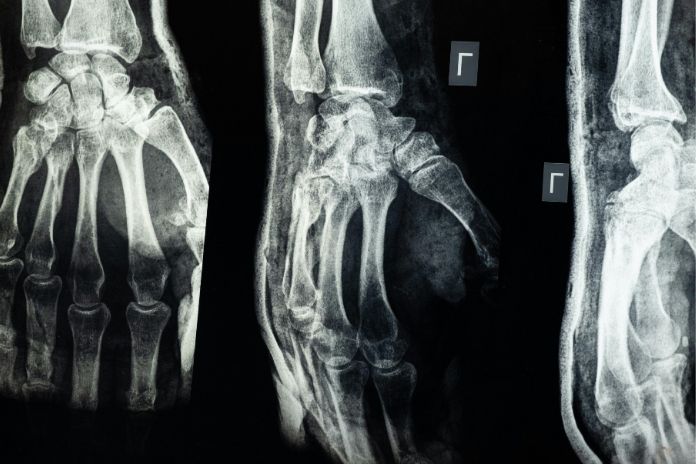

Since the crack is so narrow, early in an injury, X-rays cannot always detect it. Physicians then must utilize CT scans or MRI to detect the break. The fracture will not open up, and the bone will heal naturally in 6 to 8 weeks if immobilized early, either by a cast or splint.

3. Diagnosis Tools

Since both are such tiny cracks, diagnostic testing can be difficult. But here’s how each of them can be diagnosed:

Stress Fractures: These often won’t appear on early X-rays. MRI or bone scans are the gold standard for detecting microdamage and inflammation of the bone.

Hairline Fractures: These may appear on X-rays after a few days. Detection is possible after healing has begun, but specialized tests can confirm sooner.